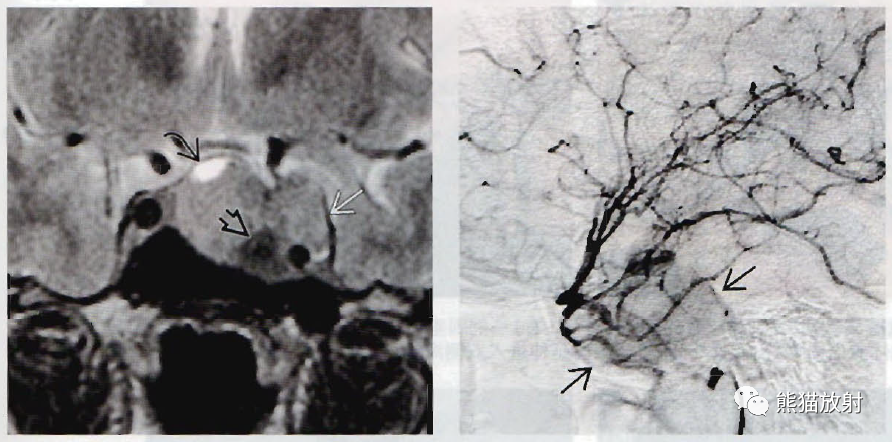

(左)冠状位图显示“雪人样”或“8字形”鞍区/鞍上肿块(弯箭)。病灶内有小的出血灶(空箭)和囊变(直箭),垂体与肿块不可区分;事实上,腺体即肿块。

(右)大体病理显示大腺瘤通过鞍膈向上延伸进人鞍上池(箭),向侧方生长进人海绵窦(弯箭),图像中去除了部分海绵窦顶壁。

(左) 冠状位T1WI MR显示典型的“8字形”或“雪人样”垂体大腺瘤。垂体与肿块不可区分;腺体即肿块。

(右) 同一位患者,矢状位T2WI薄层扫描显示肿瘤(箭)使蝶鞍(空箭)扩大、加深。相对于灰质,肿瘤呈等信号。

(左) 一例乳腺发育、催乳素明显升高的中年男性,矢状位T1WI显示巨大的侵袭性垂体大腺瘤,侵蚀斜坡,并延伸进入蝶窦和鼻咽部。

(右) 同一患者,轴位T1WI C+MR显示肿瘤侵及并破坏斜坡。肿瘤包裹右侧颈内动脉(弯箭),但没有使其闭塞。

(左) 冠状位T2WI MR显示垂体大腺瘤的囊肿(弯箭)和出血灶(空箭)。肿瘤侵及海绵窦。

(右)一例巨大的侵袭性腺瘤患者,选择性颈内动脉血管造影静脉早期侧位图显示肿瘤明显“染色”(箭)。大腺瘤常血供丰富。